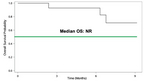

- Primary endpoint of QUILT-3.078 is overall survival; median overall survival has not yet been reached, with 19 of 23 enrolled patients alive as of January 22, 2026

- Fourteen patients have evaluable data, with the longest survival from time of disease recurrence reaching 12 months to date and ongoing

Of the 23 enrolled patients, 14 currently have evaluable clinical data and comprise the efficacy population for the current analysis. Among these evaluable patients, a total of 139 doses of combination immunotherapy have been administered. The median follow up is 6 months in the evaluable cohort. All four deaths to date occurred within the evaluable cohort, and median overall survival has not yet been reached. See figure 2.